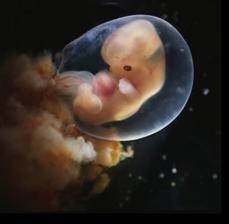

29.4. druhá KO u dr 7+3, 12,3mm a srdíčko bije

23.5. pro průkazku + odběr krve + utz 11+0 mimisek 4,2cm